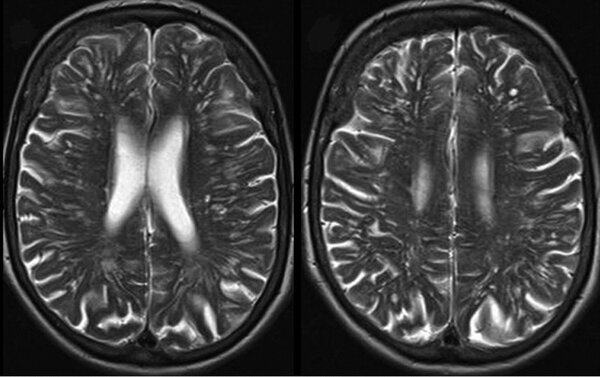

Что касается «бабочки», то такие структуры действительно есть в организме — например, в поперечном срезе спинного или головного мозга.